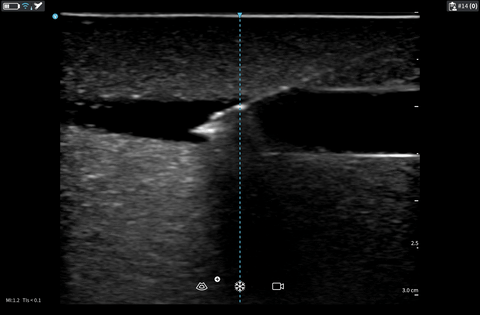

- Visualsation of the whole catheter within lumen using long axis view.

- Visualisation the snowstorm of bubbles using POCUS while flushing saline.